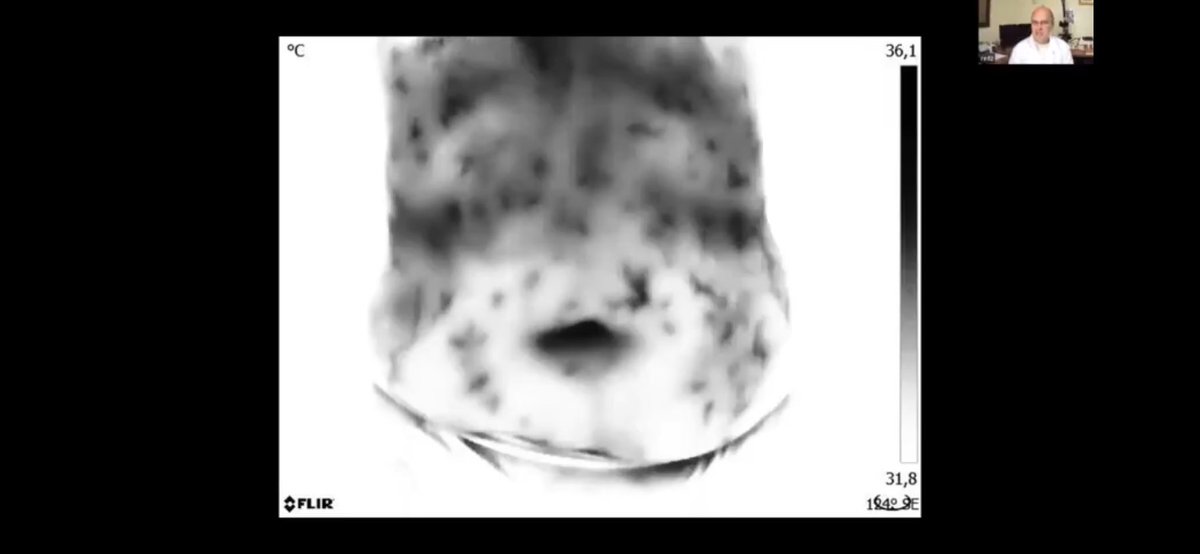

بالتصوير الحراري المحوسب الذي يكشف عن تخثر الدم بدون أعراض في نظام الأوعية الدموية بأكمله وصور الدم الحية التي تظهر جزيئات أكسيد الجرافين النانوية و تشوهات الدم الأخرى.

ظهور الجلطات في الاوعية الدموية للأرجل لشخص بعمر ٢٣ عام بعد التطعيم على الرغم من انه رياضي ولم تظهر عليه اي اعراض منها. 4️⃣